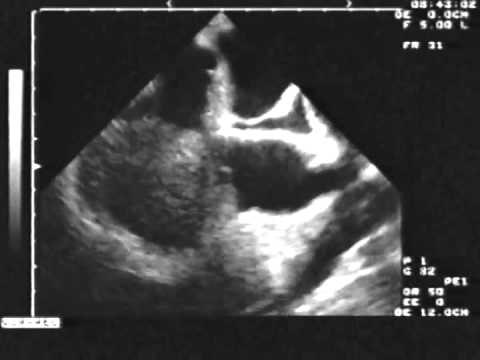

Unusual Location of a Cardiac Papillary Fibroelastoma

Atrial Myxoma in Echocardiography || Dr. Shankar Dey